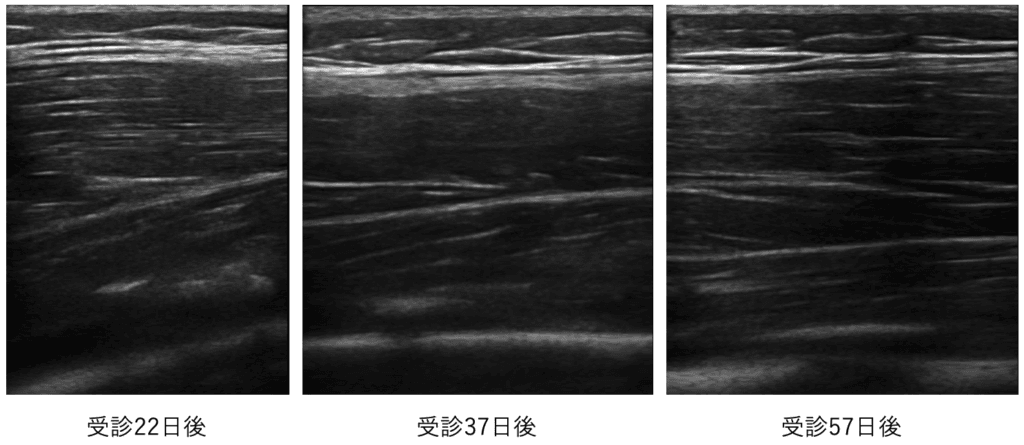

当院受診22日後から57日後までのエコー画像です。

石灰像は順調に吸収されてきていることが見てわかります。

この時期から痛みの程度に応じて徐々に運動を開始しました。

バスケットボールには受診から3.5週間後から復帰しています。